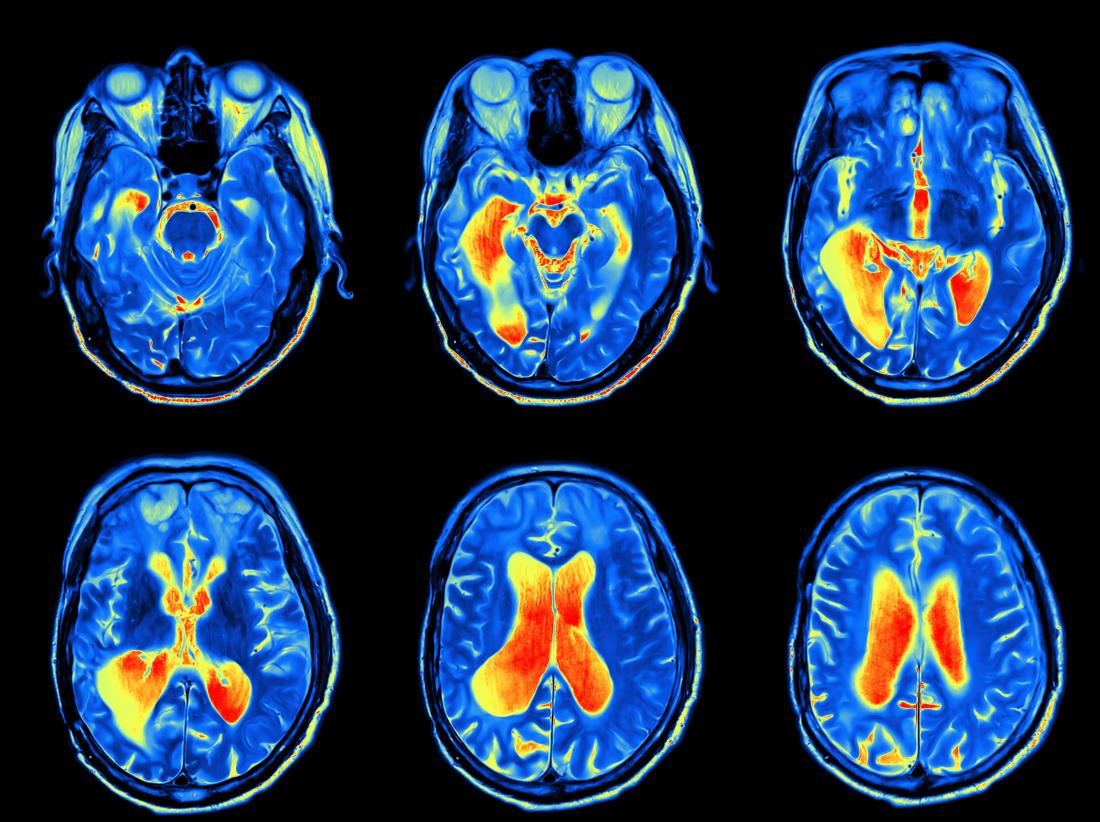

A kutatásban 30 nehezen kezelhető, 20 nem nehezen kezelhető páciens és 30 egészséges kontrollszemély vett részt. A vizsgálatok közt szerepelt egy átfogó klinikai állapotfelmérés, pszichológiai elemzés, funkcionális MR-vizsgálat, valamint transzkriptomikai (különböző szervekben, szövetekben sejttípusokban és különböző körülmények között a genomról átíródó RNS-molekulák nagy áteresztőképességű vizsgálata) és metabolomikai elemzések (specifikus, sejtszintű folyamatok által hátrahagyott „kémiai ujjlenyomatok” vizsgálata). A kutatás eredményeként sikerült kimutatni, hogy nehezen kezelhető RA-s betegeknél a gyulladásos aktivitás, valamint a krónikus fájdalom és az ezzel járó pszichés terhek a központi idegrendszert is érintik – foglalta össze dr. Gunkl-Tóth Lilla. A gyulladás, a fájdalom és a pszichológiai tényezők közötti kapcsolat feltárása és a jelátviteli útvonalak azonosítása pedig segítheti a kezelések jövőbeli fejlesztését – hangsúlyozta a kutató.

Dr. Nagy György hozzátette, hogy ez a felismerés alapvető személetváltást hozhat, mivel eddig az RA-t elsősorban ízületi betegségként kezelték. Mint mondta, a mostani eredmény nagy előrelépés:

a kutatás arra próbált rávilágítani, hogy az agyban is van egy ujjlenyomata a betegségnek, ami lényeges változást hozhat a terápiában.

A kutatásról és annak eredményeiről szóló publikáció még folyamatban van, dr. Gunkl-Tóth Lilla már több konferencián bemutatta munkájukat. Októberben Chicagóban az American College of Rheumatology (ACR) Convergence konferencián prezentálja „Multimodal Analysis Revealed Altered Brain Connectivity Patterns and Neuroinflammatory Processes in the Background of Difficult-To-Treat Rheumatoid Arthritis” („Megváltozott agyi kapcsolódási mintákat és neurológiai gyulladásos folyamatokat tárt fel egy multimodális elemzés a nehezen kezelhető reumatoid artritisz hátterében”) című előadását. Ez a konferencia az egyik legjelentősebb éves tudományos rendezvény a reumatológia területén, ahol reumatológiával foglalkozó magyar kutató még sosem kapott korábban lehetőséget, hogy bemutasson egy Magyarországon, teljesen hazai forrásokból végzett munkát. A szervezők már az absztrakt alapján odaítélték dr. Gunkl-Tóth Lillának az Emerging Investigator Excellence Award díjat, amelyet személyesen a konferencián vehet át, és amit digitális jelvény formájában fel is tüntethet majd az előadása során.